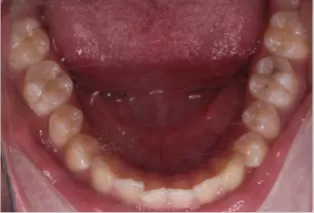

Photos intra-orales